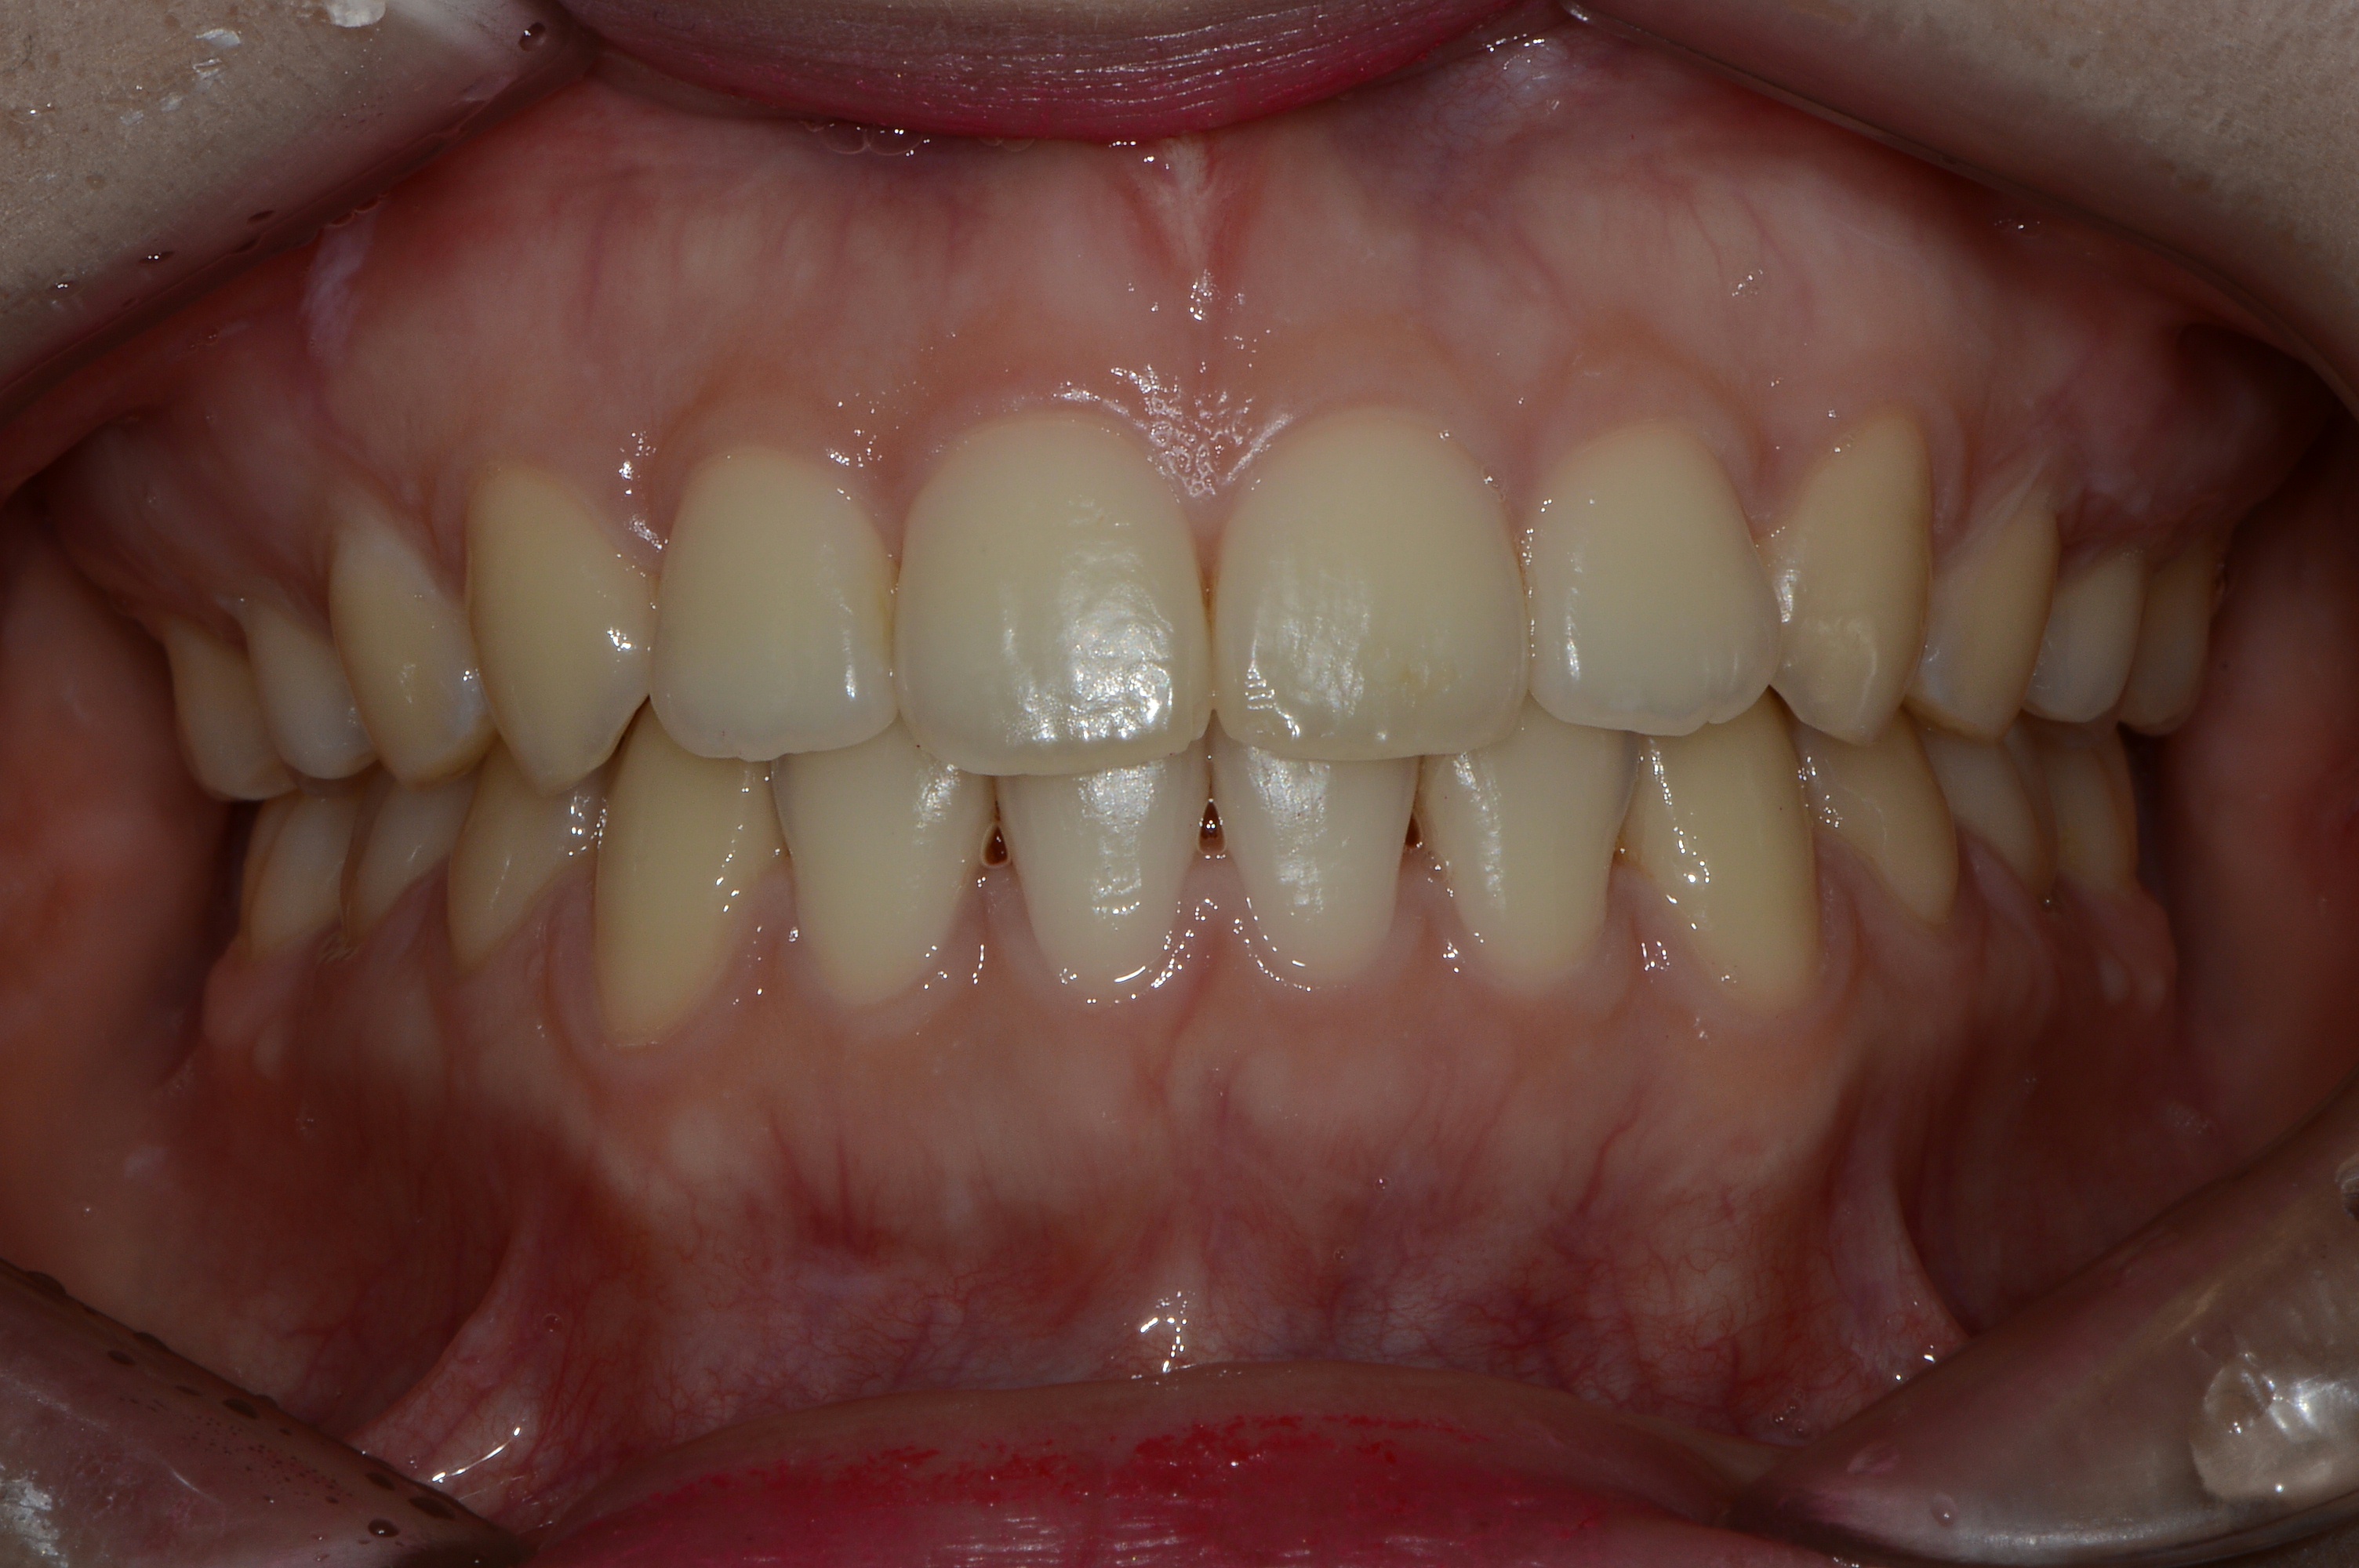

치료 후 사진입니다.